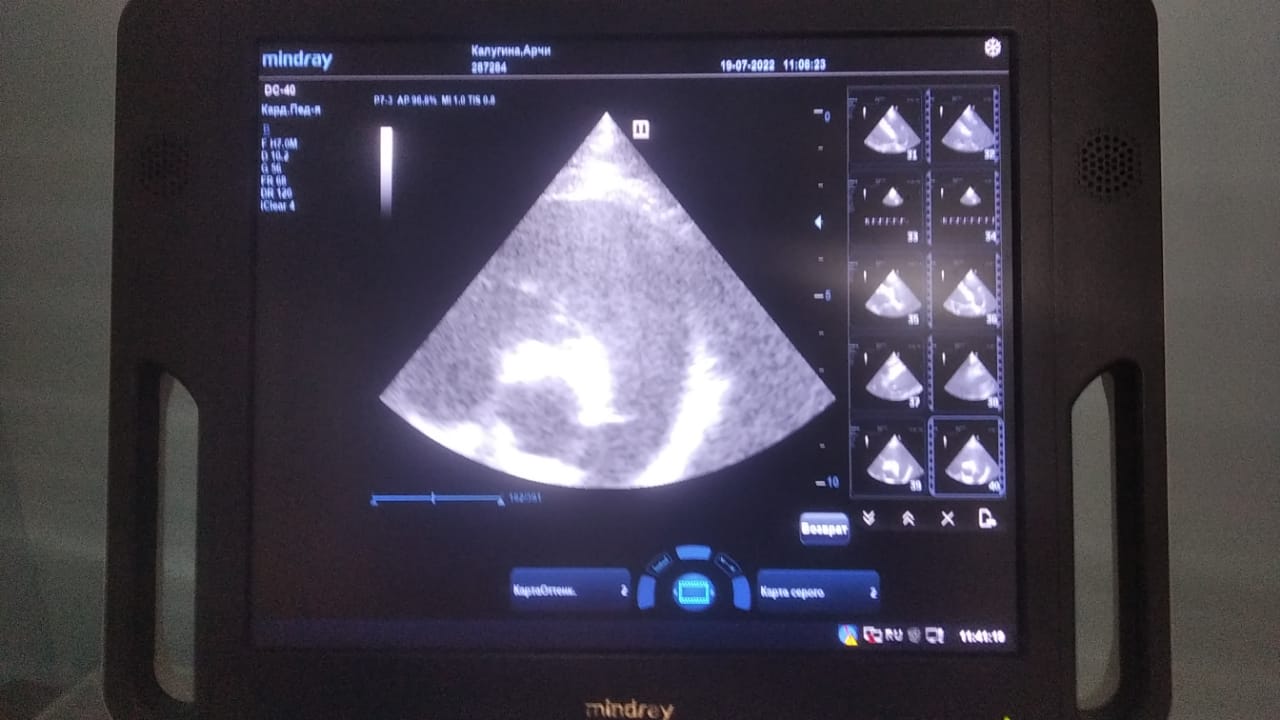

Анализы Арчи. Сердца и легких

Вложения

IMG-20220719-WA0100.jpg

IMG-20220719-WA0102.jpg

IMG-20220719-WA0104.jpg

IMG-20220719-WA0103.jpg

IMG-20220719-WA0105.jpg

Продолжение.

IMG-20220719-WA0097.jpg

IMG-20220719-WA0096.jpg

IMG-20220719-WA0099.jpg

IMG-20220719-WA0098.jpg

IMG-20220719-WA0101.jpg